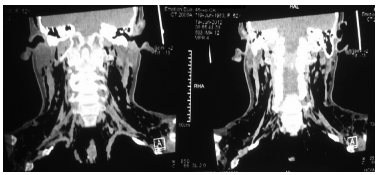

Una TAC de cuello mostró enfisema subcutáneo

importante anterior, lateral y posterior. La TAC de

tórax demostró hiperdensidades basales de predominio derecho, y enfisema subcutáneo (Figuras 1, 2 y 3). Una nueva broncoscopía realizada durante